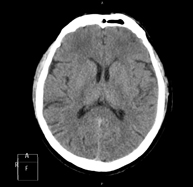

- Skull CT

Radiological test that provides high definition anatomical images of the skull (brain stem, cerebellum, cerebrum, cranial calotte, etc.) using CT (Computed Tomography) equipment. Indicated for: trauma, headache, memory disorders, sudden loss of strength in a limb or half of the body.